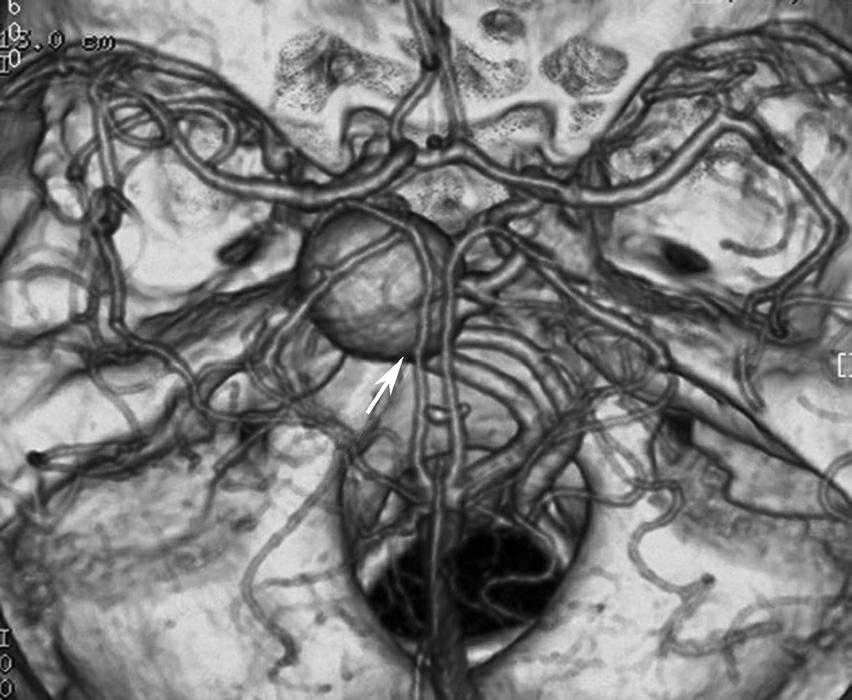

基底动脉开窗畸形的发生机制被认为是胚胎第5周时成对的胚胎性神经动脉融合障碍,或为原始侧动脉残留所致(图1-2-78)。

图1-2-78 基底动脉开窗畸形(箭)